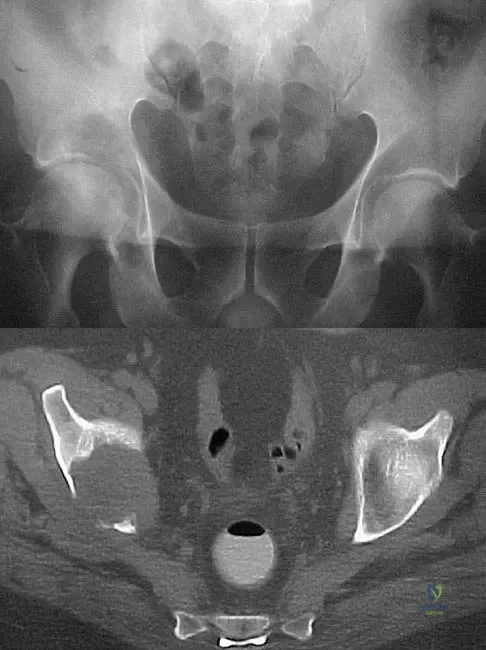

Question 17

A 50-year-old man with metastatic renal cell carcinoma has right hip pain. A radiograph and CT scan are shown in Figures 48a and 48b. The first step in management should consist of

Explanation